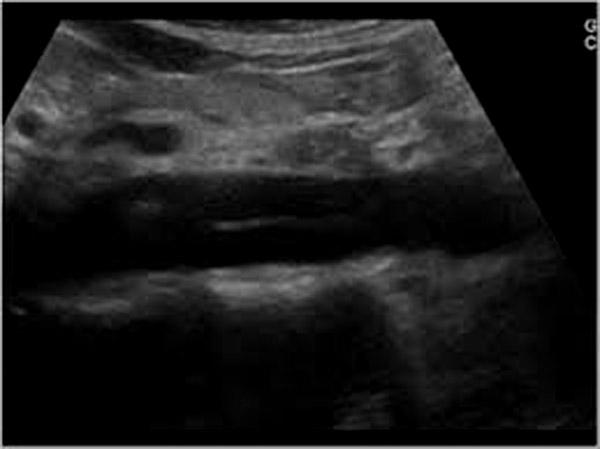

Aortic Dissection

tearing back pain

shock

headache

abdominal pain

Aortic Dissection